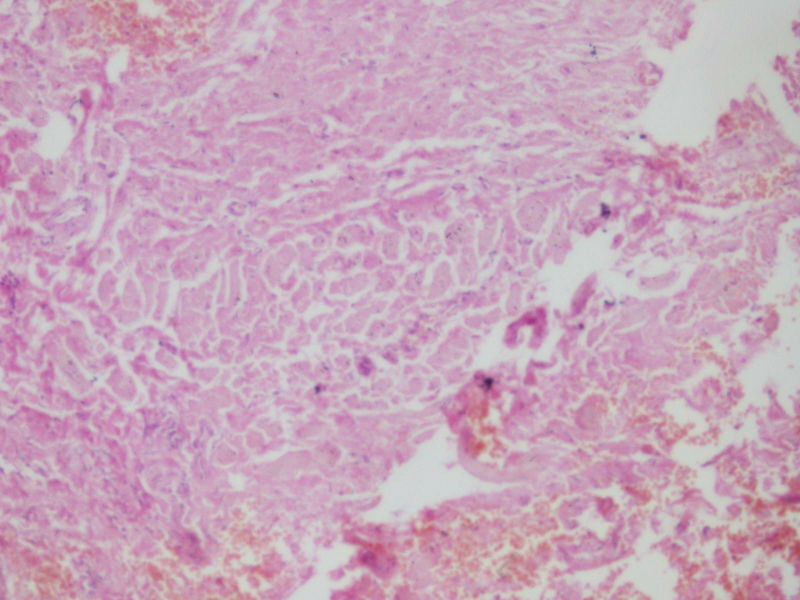

女17岁发现右大腿腘窝处一包块,渐进性增大4年,

• 右大腿包块图3

图3

肿物多大,有手术史吗?片子染得不太好,图三像异物。

据说肿物很大,但是送来只有黄豆大小,可能是只取了肿物周边的吧